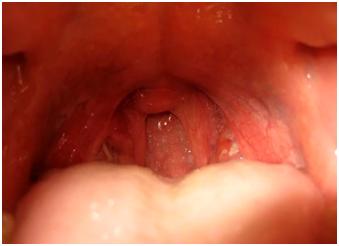

На изображении можно заметить, какие высыпания характеризуют эту инфекционную болезнь.

Фолликулярная ангина проявляется появлением небольших (примерно 1-2 мм в диаметре) гнойничков желтоватого или беловатого цвета на воспаленных миндалинах, которые слегка выпячиваются над поверхностью слизистой оболочки миндалин. На изображении показано, как выглядит горло при фолликулярной форме ангины:

Как показано на изображении, у детей симптомы ангины проявляются в значительном увеличении, покраснении и рыхлости миндалин в области нёба:

На поверхности миндалин и в лакунах образуются отложения. При попытке удалить эти отложения с помощью деревянного шпателя или ватного тампона они легко удаляются, не вызывая кровотечения из под них. Воспаленные миндалины вызывают реакцию близлежащих лимфатических узлов (подчелюстных, шейных, надключичных и других). Эти узлы увеличиваются в размерах, и при их ощупывании ощущается болезненность. Увеличение миндалин и отек окружающих тканей приводят к изменению голоса у больного — он приобретает характерный ангинозный оттенок.